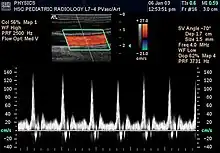

L'échographie Doppler est un examen médical échographique en deux dimensions non invasif qui permet d'explorer les flux sanguins intracardiaques et intravasculaires. Elle est basée sur un phénomène physique des ultrasons : l'effet Doppler. Elle est souvent surnommée écho Doppler.

Les échographes Doppler actuels permettent un codage couleur des flux sanguins. Par convention, les flux positifs qui s'approchent de la sonde sont codés en rouge, les flux qui s'en éloignent sont codés en bleu. Il permet ainsi une visualisation directe des flux sanguins qui se superposent à l'image en échographie bidimensionnelle en échelle de gris.